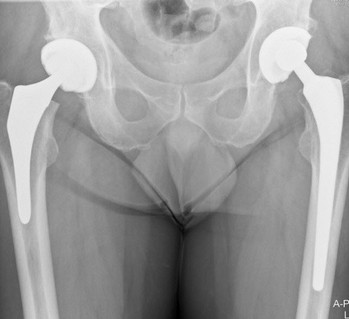

Maandag 12 september in het UMCG heupcontrole gehad. Mevr. Boss was tevreden, alhoewel de heup nog wel stijf aanvoelt. Dit kan een jaar duren voordat het weer soepel is. Er dient zich echter wel een ander probleem aan. Ik heb zo nu en dan behoorlijk last van mijn rechter knie. Deze is in 1975 geopereerd in Deventer door de bekende sportarts Rein Strikwerda en in een paar jaar later door Reinalda in Leeuwarden. Er is toen een stukje meniscus verwijderd en een vetprop. Nu ik weer de knie belast door de oefeningen bij de Fysiotherapeut is dit extra gevoelig. We hebben afgesproken dat ik eerst herstel van de heup en bij de volgende controle op 18 juni 2012 (wordt kleindochter 2 jaar en is het 1 jaar na de operatie) ook naar de knie wordt gekeken. Op de foto hieronder zijn de beide kunstheupen zichtbaar. Met lange steel 12 jaar geleden.Leren fietsen